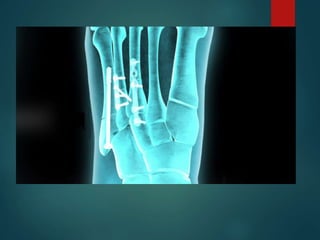

Metatarsal Fractures

▪

Oblique fracture of 5th metatarsal shaft 5TH Metatarsal base

fracture Metatarsal stress fractures

Stress fractures of the metatarsals are common in athletically

active individuals. These may not be visible on initial X-rays

but follow up images show periosteal stress reaction. This

has the appearance of fusiform bone expansion.